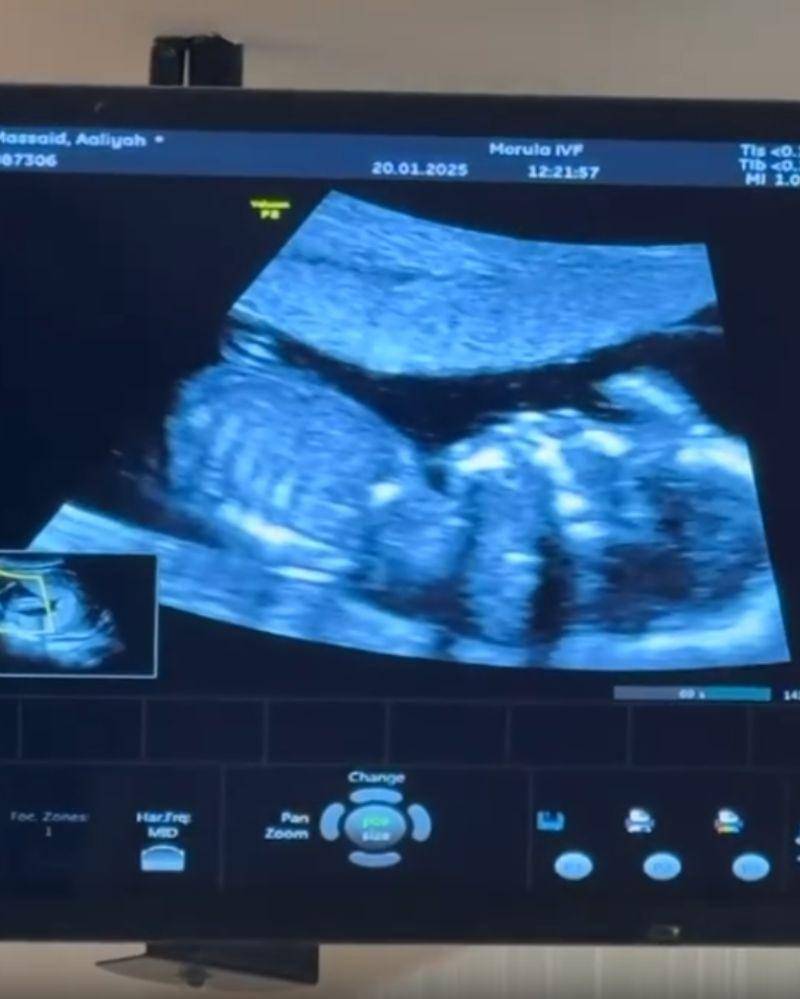

4. Sudah 4 bulan, Thariq pamerkan pemeriksaan USG terbaru

Pada unggahan lainnya, Thariq tak lupa menunjukkan hasil pemeriksaan USG terbaru Aaliyah. Terlihat pada video tersebut, pemeriksaan dilakukan setelah keduanya kembali dari perjalanan umrah.

"Hai anakku, 4 bulan papa jadi saksi perjuangan ibu @aaliyah.massaid , keram perut, pegal, mual dan nyeri mama kamu tetap happy, semua ujian dan tantangan gapernah bikin mama kamu patah. Love her the way she always does to us, dont ever hurt her, she is amazing and she is our home.. if ur seeing this nak, we want u to know that u are our little miracle dan kamu selalu ada didalam doa kami anakku," ungkap Thariq.